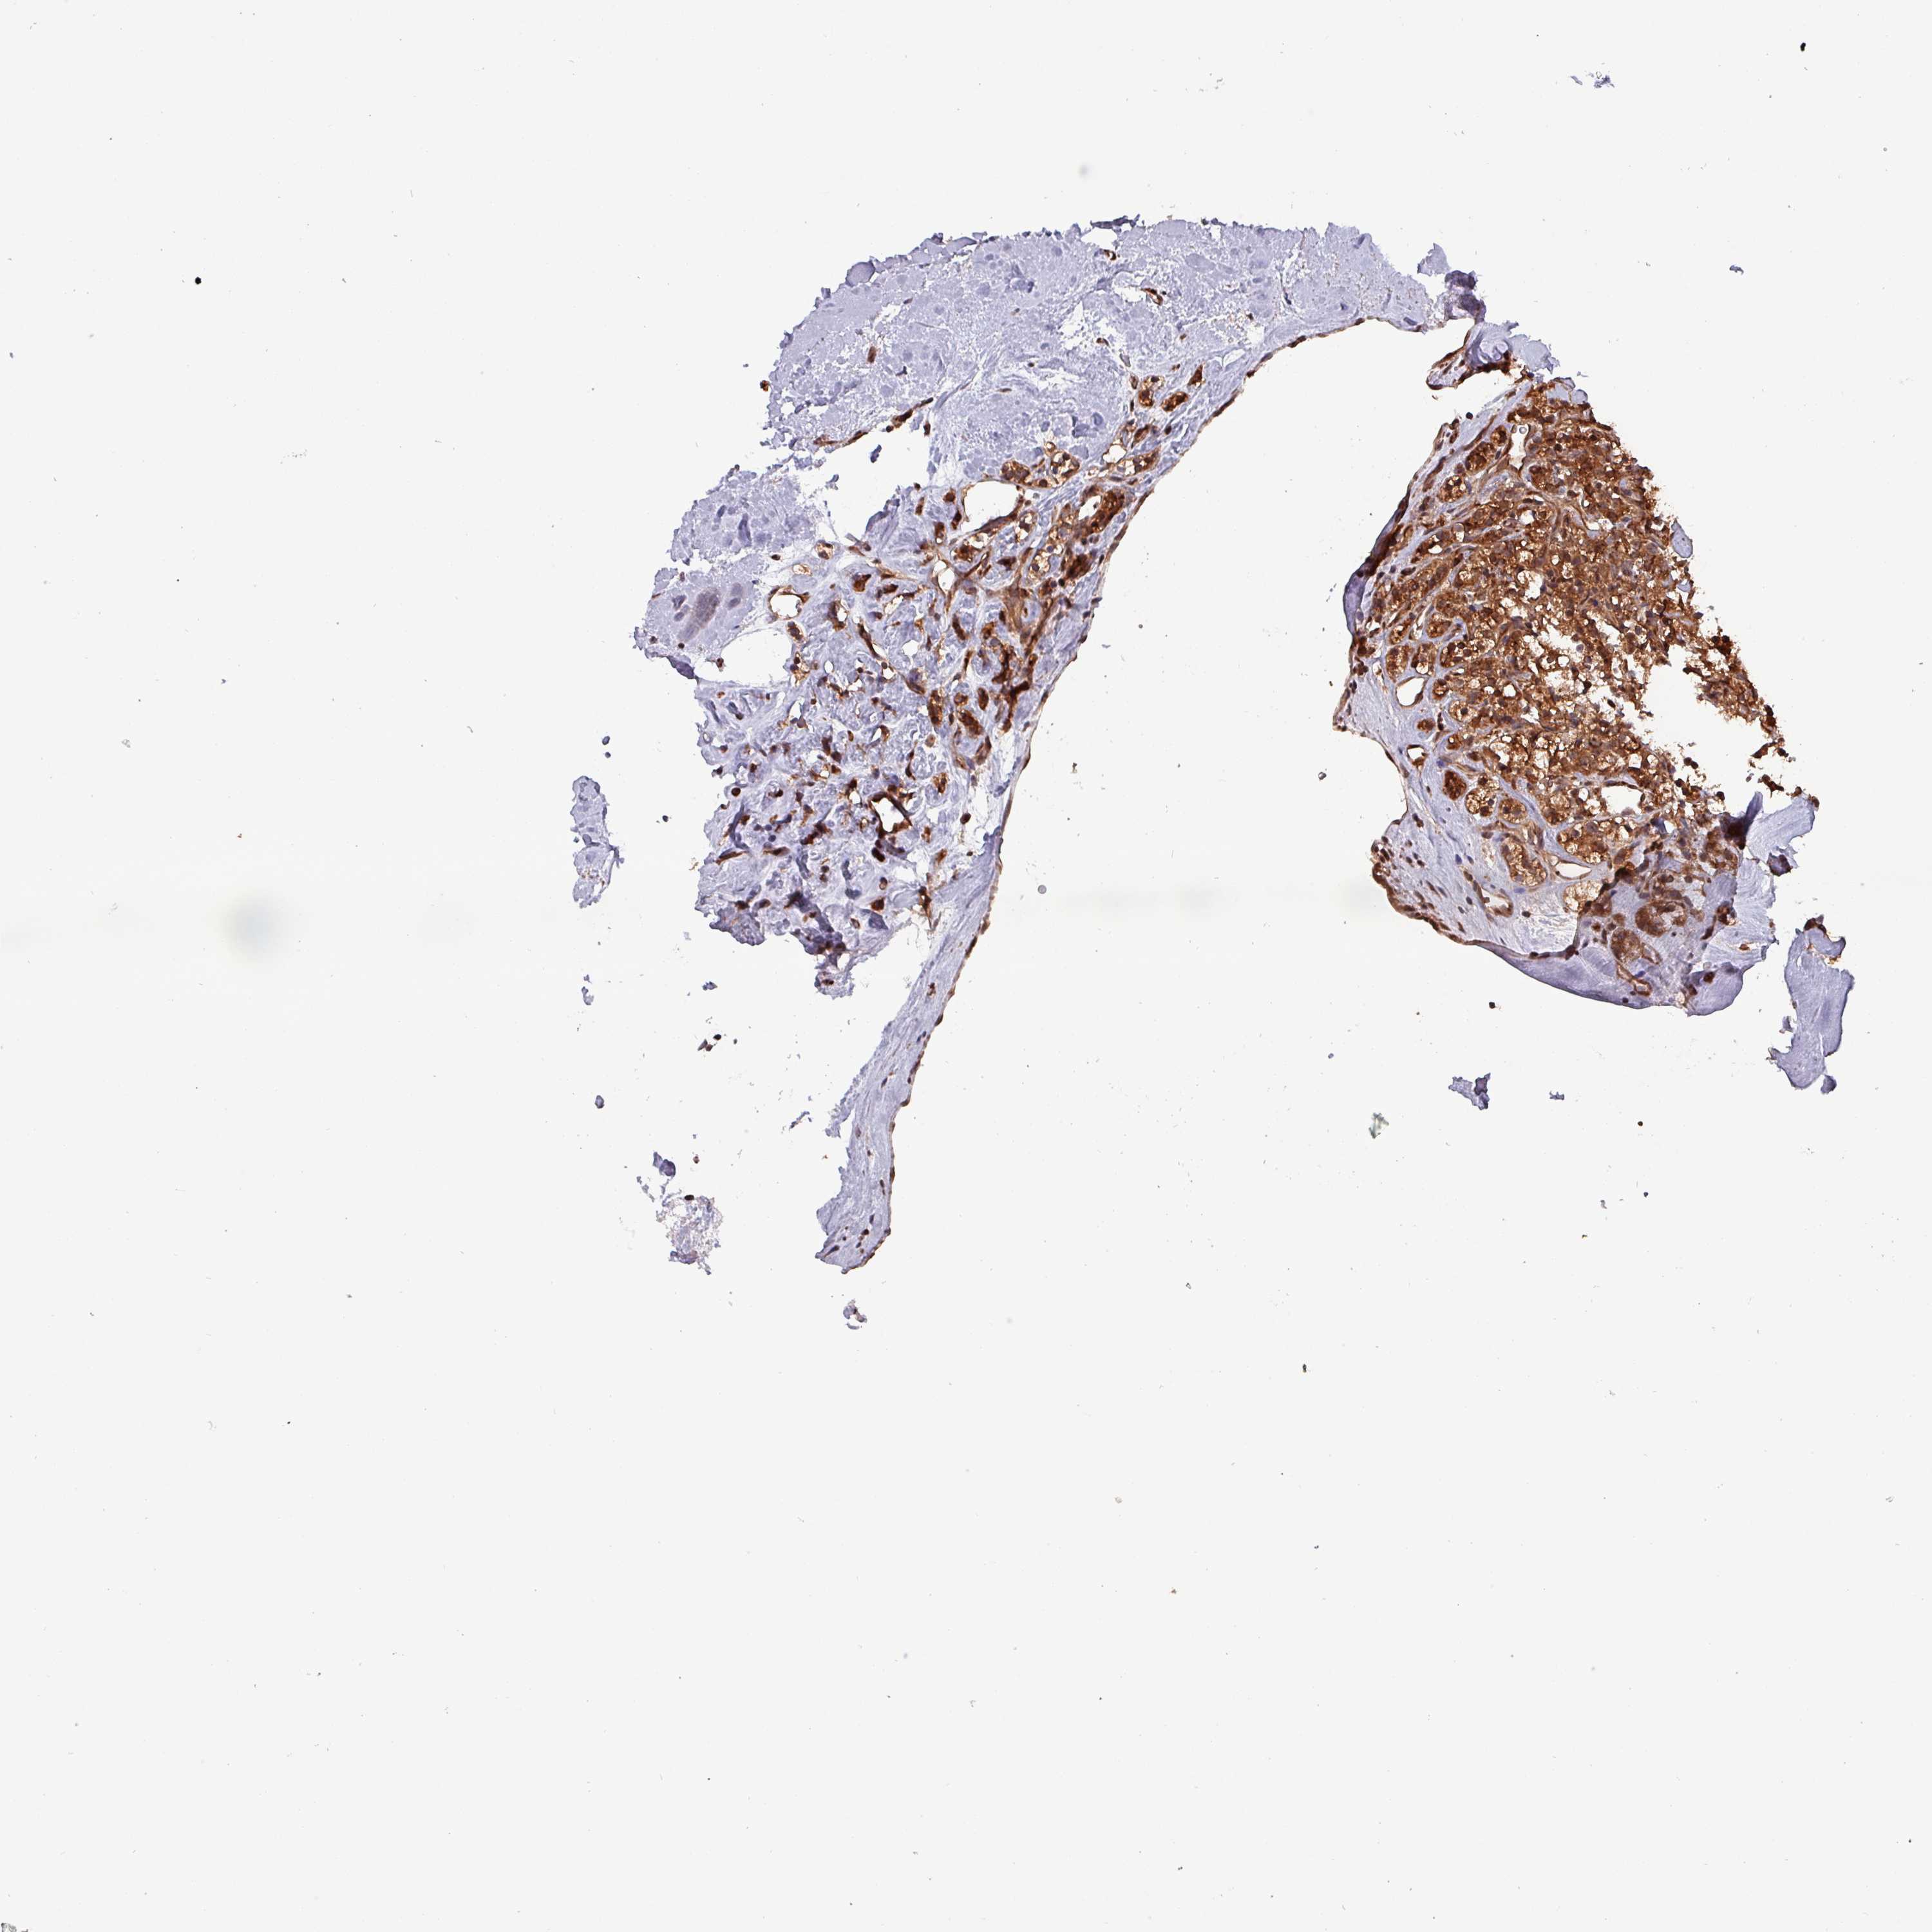

KIDNEY RENAL CLEAR CELL CARCINOMA (VALIDATION) - Interactive survival scatter ploti

The Survival Scatter plot shows the clinical status (i.e. dead or alive) for all individuals in the patient cohort, based on the same data that underlies the corresponding Kaplan-Meier plots. Patients that are alive at last time for follow-up are shown in blue and patients who have died during the study are shown in red.

The x-axis shows the expression levels (FPKM) of the investigated gene in the tumor tissue at the time of diagnosis. The y-axis shows the follow-up time after diagnosis (years). Both axes are complimented with kernel density curves demonstrating the data density over the axes. The top density plot shows the expression levels (FPKM) distribution among dead (red) and alive patients (blue). The right density plot shows the data density of the survived years of dead patients with high and low expression levels respectively, stratified using the cutoff indicated by the vertical dashed line through the Survival Scatter plot. This cutoff is automatically defined based on the FPKM cutoff that minimizes the p-score. The cutoff can be changed by dragging the vertical line or by entering a cutoff value in the square labeled "Current cut-off".

Under the Survival Scatter plot the p-score landscape (black curve; left axis) is shown together with dead median separation (red curve; right axis). Dead median separation is the difference in median mRNA expression between patients who have died with high and low expression, respectively. It is calculated as follows: median FPKM expression of dead patients with high expression - median FPKM expression of dead patients with low expression. This is intended to aid the user in visually exploring custom cutoffs and the associated p-scores and dead median separation.

Individual patient data is displayed and can be filtered by clicking on one or more of the category buttons on the top of the page. Categories describing expression level and patient information include: high, low, alive, dead, female, male and tumor stages. The scale of the x-axis can be toggled between linear and log-scale by clicking on the "x log" button. Mouse-over function shows TCGA ID, patient information and mRNA expression (FPKM) for each patient.

& Survival analysisi

Kaplan-Meier plots summarize results from analysis of correlation between mRNA expression level and patient survival. Patients were divided based on level of expression into one of the two groups "low" (under cut off) or "high" (over cut off). X-axis shows time for survival (years) and y-axis shows the probability of survival, where 1.0 corresponds to 100 percent.

PSMB8 is not prognostic in Kidney Renal Clear Cell Carcinoma (validation)

Best expression cut offi

Based on the FPKM value of each gene, patients were classified into two groups and association between prognosis (survival) and gene expression (FPKM) was examined. The best expression cut-off refers the FPKM value that yields maximal difference with regard to survival between the two groups at the lowest log-rank P-value. Best expression cut-off was selected based on survival analysis .

When clicking on this number, the vertical dashed line indicating cut-off, the interactive survival plot, and the Kaplan-Meier curve will be adjusted to show results based on the best expression cut-off.

: 16.63

Median expressioni

Median expression refers to the median FPKM value calculated based on the gene expression (FPKM) data from all patients in this dataset. When clicking on this number, the vertical dashed line indicating cut-off, the interactive survival plot, and the Kaplan-Meier curve will be adjusted to show results based on the median expression.

: N/A

Median follow up timei

Median follow up time refers to the median time (years) after diagnosis with this type of cancer, based on clinical data from all patients in this dataset.

P scorei

Log-rank P value for Kaplan-Meier plot showing results from analysis of correlation between mRNA expression level and patient survival.

N/A

5-year survival highi

5-year survival for patients with higher expression than the expression cutoff.

For melanoma and glioma, 3-year survival is shown.

5-year survival lowi

5-year survival for patients with lower expression than the expression cutoff.

TCGA RNA samplesi

RNA-seq data is reported as average FPKM (number Fragments Per Kilobase of exon per Million reads), generated by the The Cancer Genome Atlas (TCGA) .

Normal distribution across the dataset is visualized with box plots, shown as median and 25th and 75th percentiles. Points are displayed as outliers if they are above or below 1.5 times the interquartile range. FPKM values of the individual samples are presented next to the box plot.

Average pTPM 22.4

Number of samples 100